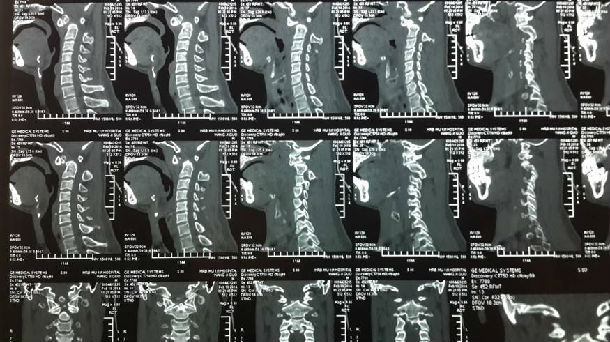

手术前CT显示:寰枢椎脱位

手术后复查CT显示:寰枢椎脱位完全复位,脊髓受压明显改善,枕颈固定位置良好,局部植骨融合。